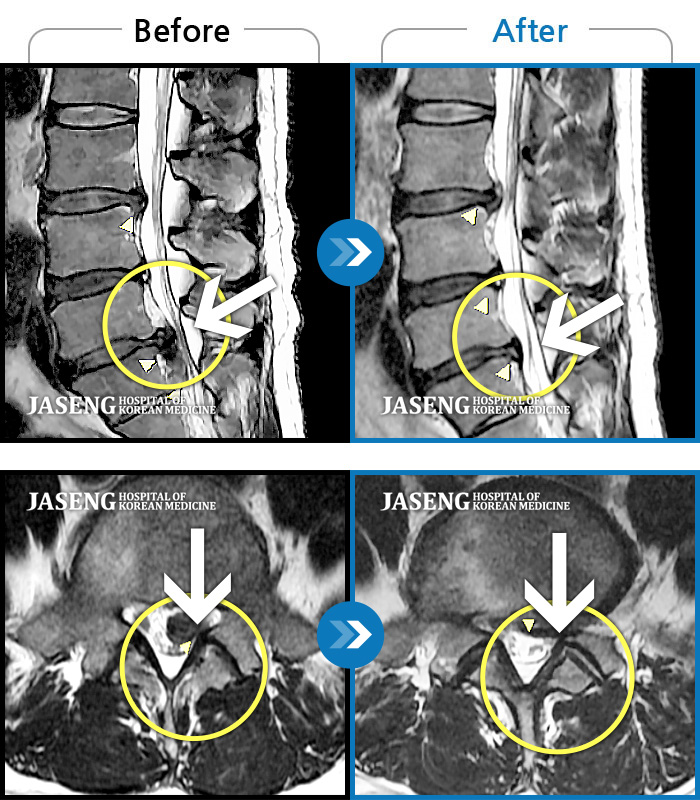

MRI 치료사례

허리디스크

해운대 · 김상돈 원장

허리가 찌릿찌릿하고 찢어질 것 같은 통증

촬영시기

2024.01.08 ~ 2025.08.12

2025.08.29